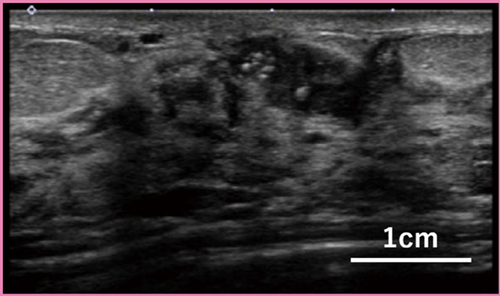

Aplio i-seriesには,スキャンと信号処理の単位を独立に最適化することにより,高フレームレートで微細・低流速な血流を描出可能とするSMIモードも搭載している。速度的には組織の動きと重なっているような低流速の血流を,組織の動きの特徴を解析して分離することで,モーションアーチファクトを大幅に低減して表示する。Aplio i-seriesでは,iBeam FormingのMulti-Beam Receiver機能により,より広範囲を高フレームレートで,クラッタを低減しつつ微細血流を映像化できるようになった(iSMI)。

Contrast Harmonic Imaging(CHI)モードによる造影超音波も可能であり,SMIを併用した造影SMIでは,血流がより感度良く描出される。図2は,PLI-1205BXによる乳腺腫瘤の造影SMI画像である。腫瘤内および周囲の詳細な血流形態が映像化されている。iDMSプローブであるPLI-1205BX, PLI-2004BXは,断層像のスライス厚を調整するSlice Thickness Control機能にも対応しており,スライス方向に立体的に広がる血管構造を1枚の断層像内に連続性良く描出することができる。

図2 高周波プローブ「PLI-1205BX」の乳腺造影SMI画像

(画像提供:高松平和病院・何森亜由美先生)